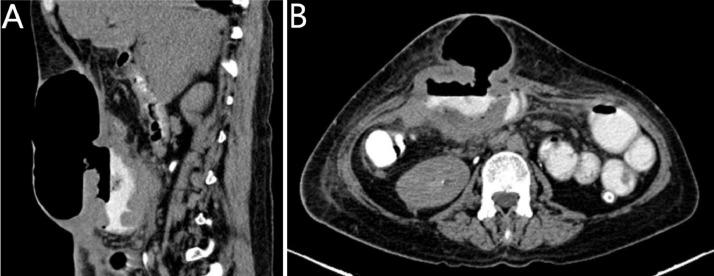

卵巢成熟性囊性畸胎瘤恶变伴小肠转移,右卵巢偶然发现浆液性囊腺瘤碰撞瘤。

Malignant degeneration of mature cystic teratoma of the ovary with small bowel metastasis incidental serous cystadenoma collision tumor of the right ovary.

Mature Cystic Ovarian Teratoma (MCOTs) are the most common benign ovarian neoplasms, representing around 20% of all ovarian neoplasms with middle age women representing the majority of patients. They usually include two germ cell layers being well differentiated and rarely they demonstrate malignant transformation with squamous cell carcinoma being the most common malignant transformation. In our case, we report an interesting case of a 45 years old lady who was unfortunate to have a MCOT with malignant degeneration and distant metastasis. We concluded that MCOT malignant degeneration is rare, however, if not caught early, mortality can be high. MCOT, Ovary, Small Bowel, Teratoma, Collision tumor.

摘要

成熟囊性卵巢畸胎瘤(MCOTs)是最常见的卵巢良性肿瘤,约占所有卵巢肿瘤的20%,患者以中年女性为主。它们通常包含两个分化良好的胚层,很少发生恶变,其中鳞状细胞癌是最常见的恶变类型。在我们的病例中,我们报告了一例有趣的病例,一名45岁女性不幸患有发生恶性变和远处转移的成熟囊性卵巢畸胎瘤。我们得出结论,成熟囊性卵巢畸胎瘤恶性变很少见,然而,如果不及早发现,死亡率可能很高。成熟囊性卵巢畸胎瘤、卵巢、小肠、畸胎瘤、碰撞瘤。